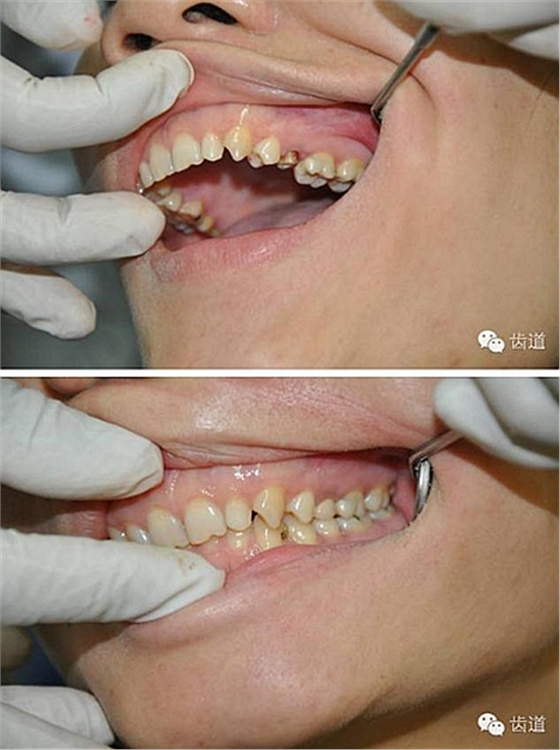

如果肩臺制備不到位或不制備肩臺,全冠戴入后冠邊緣就會形成異物懸突,刺激牙齦,引起齦發(fā)炎出血,時間一長甚至?xí)?dǎo)致牙冠腐爛。

1.修復(fù)體邊緣密合性檢查困難。(如果修復(fù)體邊緣形成懸突,不密或 不光滑,容易對牙齦產(chǎn)生機械性和細(xì)菌性刺激)

2.如果印模齦緣處不清晰,技工將很難掌握肩臺的位置,最終修復(fù)將有可能出現(xiàn)內(nèi)冠邊緣懸突和肩臺懸突的問題。

內(nèi)冠邊緣懸突是導(dǎo)致牙齦變色的"罪魁禍?zhǔn)?quot;

肩臺懸突易出現(xiàn)繼發(fā)齲